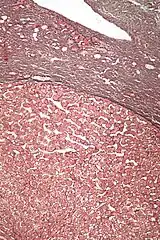

Micrograph of a hepatic adenoma (bottom of image). H&E stain

Hepatic adenomas are, typically, well-circumscribed nodules that consist of sheets of hepatocytes with a bubbly vacuolated cytoplasm. The hepatocytes are on a regular reticulin scaffold and less or equal to three cell thick.

The histologic diagnosis of hepatic adenomas can be aided by reticulin staining. In hepatic adenomas, the reticulin scaffold is preserved and hepatocytes do not form layers of four or more hepatocytes, as is seen in hepatocellular carcinoma.

Cells resemble normal hepatocytes and are traversed by blood vessels but lack portal tracts or central veins.